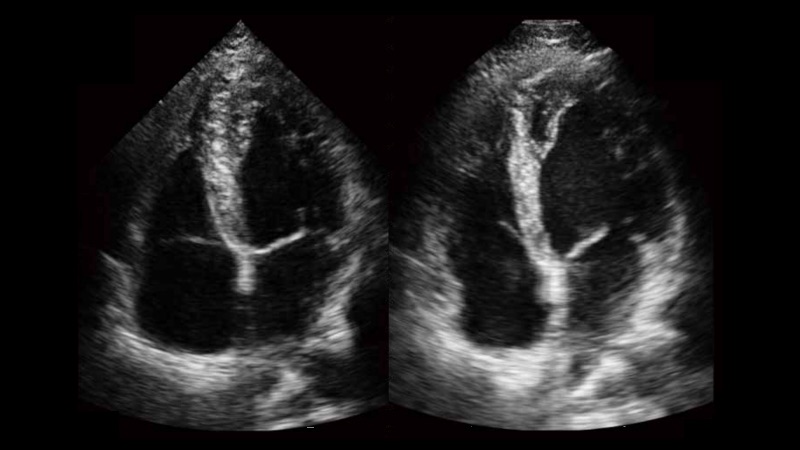

自動識別收縮和舒張末期心肌內(nèi)膜,自動計算射血分數(shù)EF值。